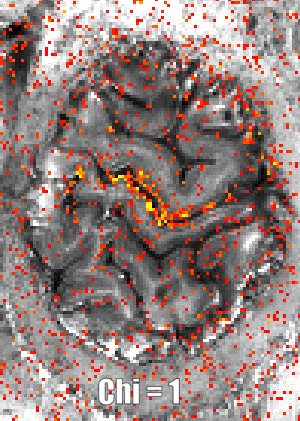

VASO_gif renzohuber July 1, 2018July 1, 2018 Published by renzohuber View all posts by renzohuber Published July 1, 2018July 1, 2018